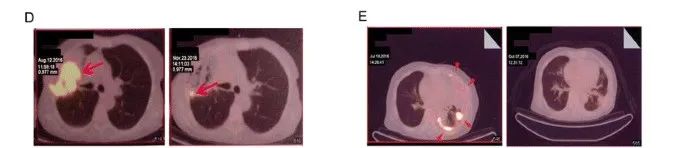

需要注意的是,当肿瘤小于0.5cm时,传统的CT检查很难观察到,因此,一旦发现确切的病灶,往往为时已晚,肿瘤已经完全苏醒复发,甚至播散至全身!

知名肺癌专家杨跃教授说:血液检测的动态随访和监测,可以更为精准地发现患者术后复发的趋势和苗头,从而给了我们主动出击、通过辅助治疗预防复发的策略选择,而不仅仅只是守株待兔,等到复发之后再应对。

血液检查的发展(如ctDNA、cfDNA),使得我们能够提前对复发的风险进行预测。通过对循环血里面肿瘤细胞、肿瘤碎片(甚至是DNA水平的肿瘤碎片)的检测,获取肿瘤复发的信号。这对于早、中期肺癌术后复发风险的预测,具有非常大的帮助。当前国家层面也在通过医疗保险帮助患者覆盖血液检测的成本。手术后的患者如果想密切监测血液中的循环肿瘤细胞水平,可以致电全球肿瘤医生网医学部了解详情。